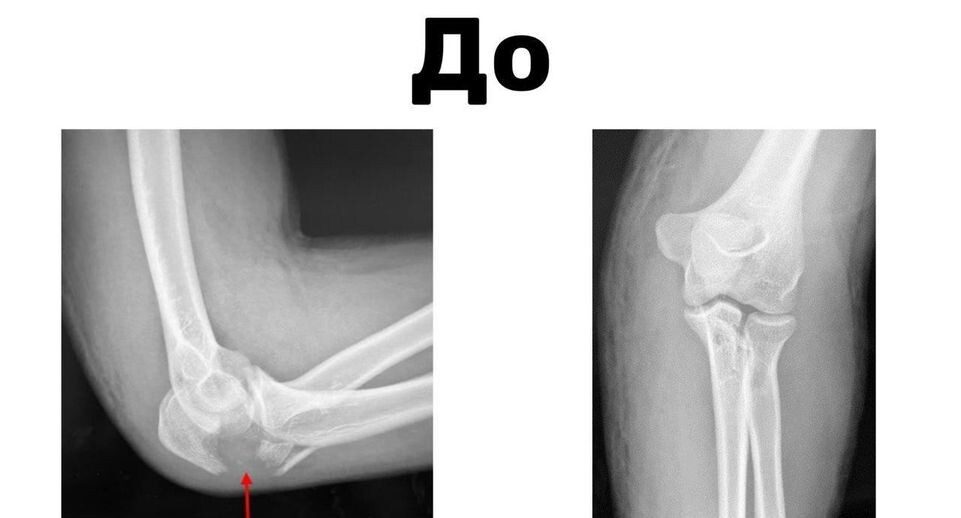

Врачи Детского клинического центра имени Л. М. Рошаля помогли 17-летнему пациенту со сложным переломом локтевого сустава. Подросток получил травму на горнолыжном курорте в Сочи.

Специалисты детского центра тщательно осмотрели пациента и приняли решение провести операцию.

«Мы получили доступ к сломанной кости, выполнили репозицию — восстановили правильные анатомические взаимоотношения в суставе, сопоставив все костные отломки и зафиксировали их в правильном положении с помощью металлической пластины», — пояснил заведующий травматологии и ортопедии № 2 Алексей Иванов.

Вмешательство длилось около часа. Юного пациента уже выписали. Через полгода пластину удалят, после чего молодой человек сможет пользоваться рукой без ограничений.